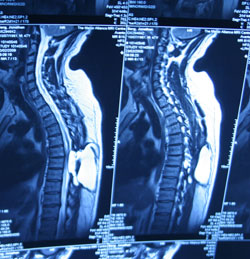

‘I’ll arrange an MRI scan and for him to see an orthopaedic surgeon,’ he said. ‘It’s probably stress.’

I took Jonathon for his scan, but we had to wait three weeks for the results. By then, he could barely swallow. And at the doctor’s… ‘You need to take him to hospital now,’ he told me. ‘Don’t wait for an ambulance, I’ve called ahead and told them to expect you.’

It was painful for him to stand. Hospital tests revealed why. ‘We found a hole in your spinal cord,’ his doctor said. ‘It’s been leaking spinal fluid into your brain. That’s what caused your haemorrhages.’

‘He should make a full recovery,’ the doctor said. Jonathon had to have two ops to patch up his spine.